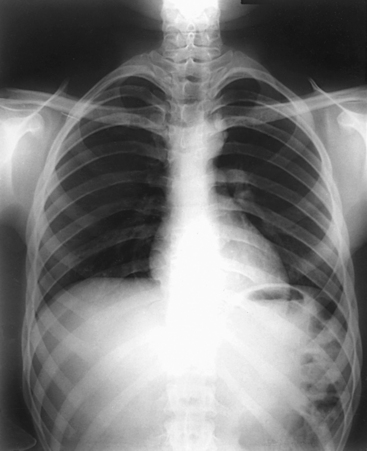

Structures shown: PA projection of the thoracic viscera shows the air-filled trachea, the lungs, the diaphragmatic domes, the heart and aortic knob, and, if enlarged laterally, the thyroid or thymus gland (Fig. 10-32). The vascular markings are much more prominent on the projection made at the end of expiration. The bronchial tree is shown from an oblique angle. The esophagus is well shown when it is filled with a barium sulfate suspension.